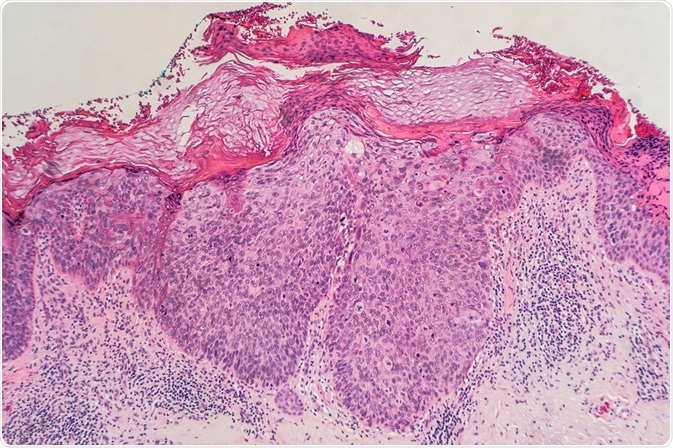

Bowen’s disease (BD) is neither a genetically transferable disease, nor one caused by direct contact through skin, but can occur anywhere in the body and is usually seen on the lower legs. Red scaly patches, warts, or spots on the epidermis are the general symptoms of this disease.

Often, the skin becomes sore, itchy, and sometimes bleeds and forms scab due to scratches. This disease is precancerous, in which lesions grow visibly on the upper layer of the skin. It does not cause any serious damage to the vascular bundle and endodermis.

The patches seem red-brown in color with a mild inflammation. They resemble sclerosis and a thin form of psoriasis, dermatophyte infection, or dermatitis.

Due to intradermal carcinoma, persistent and non-elevated patched red scaly plaques occur, with a possibly cancerous outcome. These proliferate to atypical squamous cells, which resemble fish scales.

The effect of SCC in situ varies with the locations. Usually it occurs on skin when exposed directly to sun rays, affecting the scalp, top layer of lips, and back of ears. Possibilities are there to occur anywhere on the body, including inside buccal cavity and in the genital areas. BD presents in the skin as a slow growing, well-demarcated plaque with uneven borders and scaled skin layers or crusted layer.